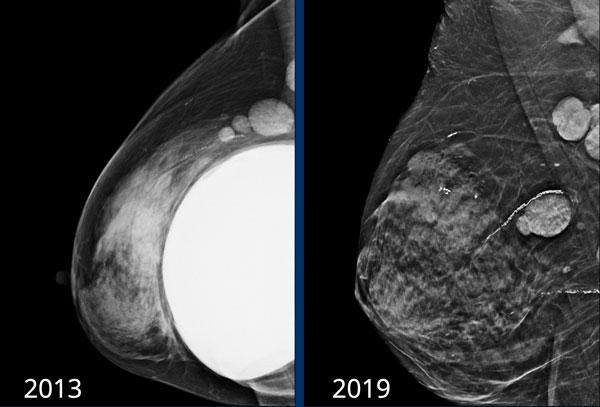

Các u hạt silicon còn tồn lại sau khi tháo bỏ túi ngực do vỡ ngoài bao xơ trước đó vào năm 2013.

U hạt silicon có thể biểu hiện dưới dạng các khối có hình thái đáng ngờ và động học ngấm thuốc tương phản từ trên MRI vú, hoặc tăng hấp thu FDG trên PET-CT.

Chúng có thể xuất hiện ở ngoại vi của túi ngực hoặc trong mô vú sau khi vỡ.

Sự hiện diện của túi ngực silicon và nhận thức về khả năng vỡ túi cũng như hình thành u hạt silicon có thể giúp đưa ra chẩn đoán chính xác (tài liệu tham khảo).

Trên nhũ ảnh năm 2019 cho thấy vôi hóa bao xơ lan rộng và hình dạng rất tròn của túi độn ngực.

Điều này gợi ý co rút bao xơ của túi độn.

Tại lần tái khám năm 2020, đường bờ đã thay đổi và hiện có silicone thoát ra ngoài bao xơ, đây là dấu hiệu xác định của vỡ túi ngoài bao xơ (mũi tên).

Bệnh nhân cao tuổi này không muốn phẫu thuật mà chỉ muốn tầm soát khả năng ác tính.

Tại lần tái khám năm 2022, hình ảnh không thay đổi nhiều. Gel silicone hiện đại có độ kết dính cao hơn và ít có xu hướng lan rộng hơn.